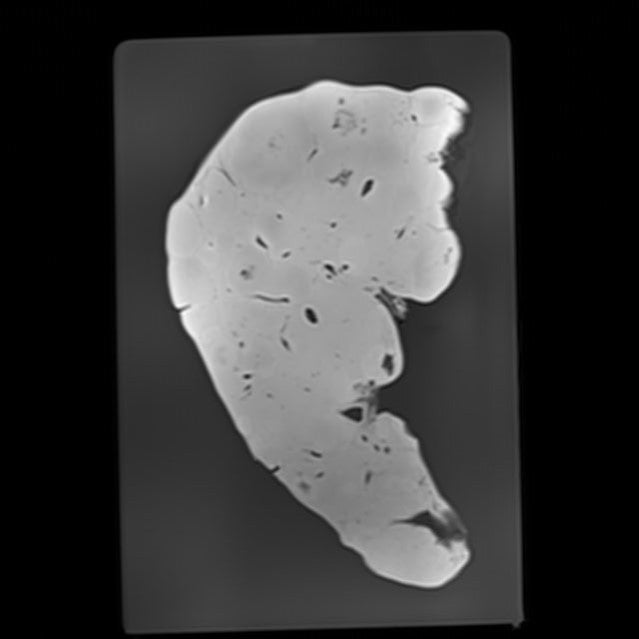

Liver - Normal